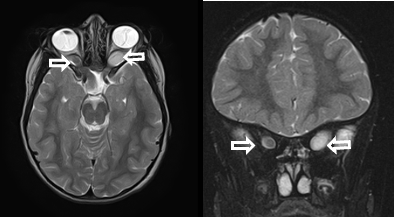

[NF2]

• 진단기준: 다음 중 하나를 만족

• 양측 vestibular schwannoma 가 존재

• 편측 vestibular schwannoma 가 있는 환자가 NF-2를 가진 부모/형제/자식이 있거나 수막종/신경집종/신경교종/신경섬유종/후피막하 수정체 혼탁 중 두가지 이상이 있는 경우